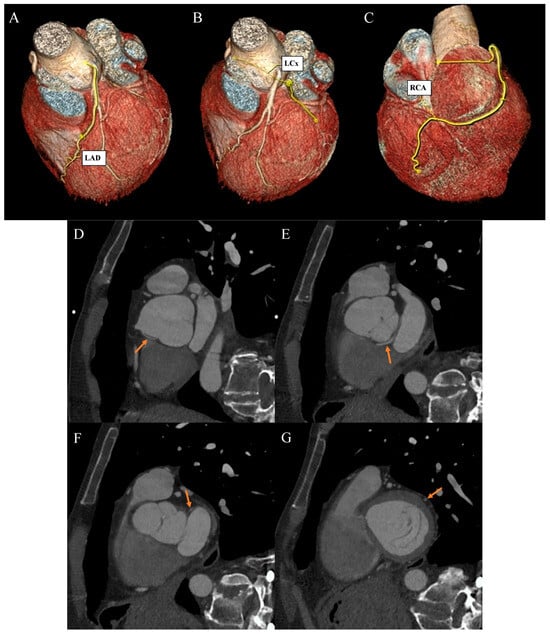

Ehlers–Danlos syndrome (EDS) encompasses a spectrum of heterogeneous, heritable disorders affecting connective tissue. According to the 2017 international classification of EDS, there are 13 subtypes. A rare 14th subtype was found in 2018. Each subtype has unique aspects, and a genetic cause has been identified in all subtypes except hypermobile EDS [1]. Clinical manifestations arise from the pervasive fragility and weakness of the soft connective tissue. Apart from manifestations in the skin, ligaments, joint and internal organs, there are subtypes of EDS which affect blood vessels and cardiac valves. These subtypes confer a higher risk of cardiac valve insufficiency, aneurysms, dissections, or ruptures of arteries, including coronary ruptures [2]. The estimated prevalence of EDS approximates 194.2 cases per 100,000 individuals [3]. Here, we present a case of a 34-year-old man with normal body weight, with hypermobile EDS, type 2 diabetes mellitus, chest deformity, aortic valve regurgitation, and aortic bulb aneurysm characterized by an axial diameter measuring approximately 5 cm (Figure 1). The patient had severe rotational scoliosis of the Th-L spine, with a significant deepening of the thoracic kyphosis and lumbar lordosis. There was a decrease in the AP dimension of the chest, a deformation of the ribs with a decrease in the width of some intercostal spaces, and a secondary widening of the width of other intercostal spaces. The patient underwent elective spine surgery to correct severe rotational scoliosis of the T-L spine. After postoperative rehabilitation, the patient underwent a thorough assessment of eligibility for aortic bulb aneurysm and aortic valve replacement surgeries. Consequently, a coronary computed tomography angiography (CCTA) was performed five months after the spinal surgical intervention. The CCTA revealed an absence of the left main (LM) and the right coronary artery (RCA) dominance. Significantly, the left circumflex artery (LCx) exhibited an ectopic origin from the right sinus of the valsalva, demonstrating a retroaortic course in the proximal segment and a typical course in the distal segments (Figure 2). Furthermore, the presence of a coronary–pulmonary arterial fistula (CPAF) in the CCTA was visualized. A vessel with an approximate diameter of 0.3 cm originated from the right sinus of the valsalva and progressed anteriorly and then towards the left, traversing anteriorly to the right ventricular outflow tract. Thereafter, this vessel was visible to the left of the main pulmonary artery, ultimately divided into multiple narrow segmentally aneurysmally dilated and tortuous fistula vessels. The fistula vessels showed communication with the proximal segment of the main pulmonary artery (Figure 3). Moreover, the imaging revealed the presence of an additional right pulmonary vein (Figure 4). The CCTA revealed calcifications within the aortic valve. The patient received a qualification card for surgical treatment, was informed about the high surgical risk, and is awaiting the operation.

Figure 2. Coronary artery computed tomography angiography. Coronary artery anomaly. (A) Volume-rendering technique reconstruction. Left anterior descending (LAD) artery with a direct origin from the left aortic bulb sinus. (B) Volume-rendering technique reconstruction. Distal left circumflex artery (LCx) segment as a continuation of the branch located between the aortic bulb and left atrium wall. (C) Volume-rendering technique reconstruction. Dominant right coronary artery (RCA) with a typical course. (D) Multiplanar reconstruction. Oblique view. The arrow indicates the ectopic origin of LCx from the right aortic bulb sinus. (E) Multiplanar reconstruction. Oblique view. The arrow indicates the retroaortic course of the proximal LCx segment. (F) Multiplanar reconstruction. Oblique view. The arrow indicates the course of the medial LCx segment between the aortic bulb and left atrium. (G) Multiplanar reconstruction. Oblique view. The arrow indicates a typical course of the distal LCx segment.